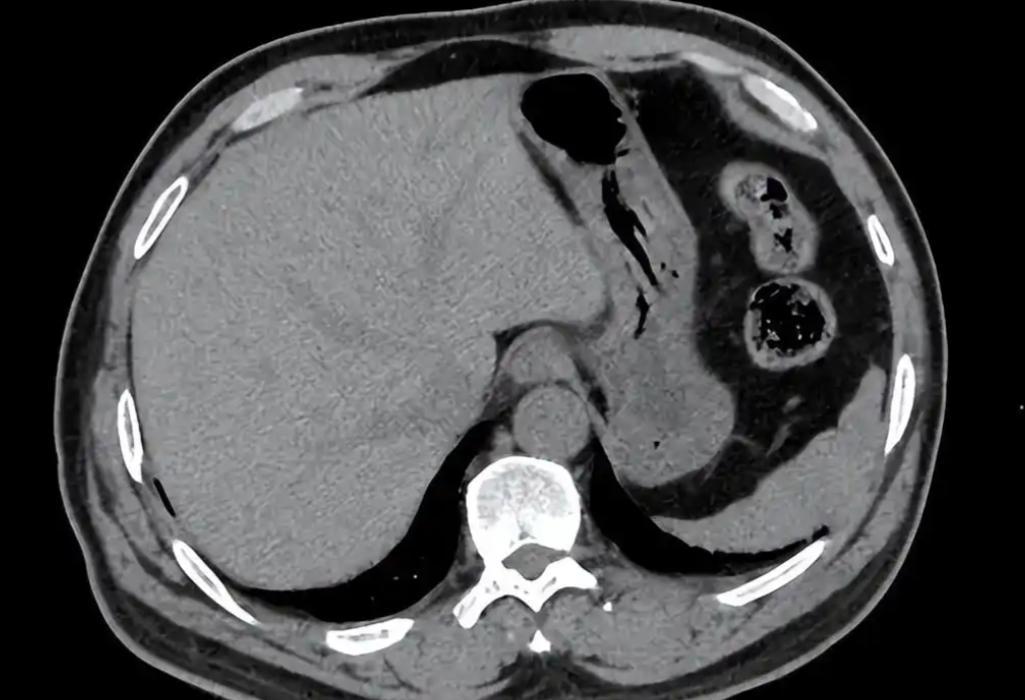

47岁女子确诊胰腺癌,医生责怪:半年前身体出现异常,为何不就医 胰腺癌这病,听起来就让人发怵,不是因为它有多罕见,而是因为发现得太晚。有医生说过,真正能早期确诊的胰腺癌患者,十个里头都凑不出一个。 有的人身体明明早就发出信号,可就是不当回事,硬生生拖成晚期。像那位47岁的确诊患者,医生在看过她的检查报告后只问了一句:半年前开始体重掉那么快,怎么都没查一查? 胰腺癌早期其实不是完全没动静,只是那些异常太容易被误解。体重突然下降、吃饭没胃口、稍微吃点油腻就恶心,很多人以为是胃不好、太累、工作压力大,还有人说“年纪上来了,吃少点正常”。 问题就在这儿,等到真正疼了、黄疸出来了、连背都开始酸胀,往往已经是肿瘤压迫到了胆总管甚至侵犯了神经。 还有不少人会忽视排便的变化。胰腺分泌胰酶参与脂肪代谢,一旦胰腺出了问题,脂肪消化吸收就会出错,大便会变得发白发黏、漂浮在水面。 这种情况叫脂肪泻,但因为没有腹泻的感觉,很多人不放在心上。吃完饭肚子总有点不舒服,排便不成型,这些在门诊经常听到,但真正愿意去做个影像学检查的,几乎没有。 有些人揉揉腰、贴个膏药觉得过两天就好了,但胰腺的位置比较深,早期癌变时压迫或浸润后腹膜,疼痛往往是往背后放射的,而且晚上更明显,平躺时加重,坐起来反而缓解。 这种特征其实很典型,但因为很多人日常久坐、劳累,也经常有腰背痛,真痛起来也没太放在心上。 更有意思的是,有些胰腺癌患者早期唯一的表现就是血糖控制变差。特别是原本血糖一直正常的人,突然出现波动,或糖尿病病人突然控制不住血糖,用药效果变差,这时候也要留心胰腺功能的问题。 有研究统计,大约有一成以上的胰腺癌患者在确诊前半年出现新发糖尿病,或者糖代谢异常,但因为没有其他症状,大多被当成单纯代谢问题处理了。 胰腺癌最可怕不是它难治,而是它太会藏。身体其实不是没提醒,只是被人太容易忽略。不是每一个消瘦都代表癌,但每一个持续性的身体变化,都值得认真去查清楚。 尤其像胰腺这种沉默的器官,出事的时候不吵不闹,等你真感受到它的存在,往往就已经太晚了。身体的声音听起来可能微弱,但从来都不是没在说话。只看表面,就很容易错过救命的信号。